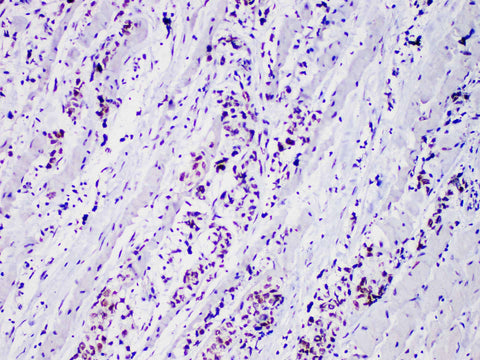

Myo D1 Monoclonal Antibody Stored at -20°C

Applications IHC-P

Cellular Localization nucleus

Tissue Specificity Rhabdomyosarcoma

Tropomyosin regulatory protein (MyoD1) is a marker of rhabdomyosarcoma, which is mainly used for the diagnosis of rhabdomyosarcoma. A few non-muscular tissues including glandular epithelium, neuroblastoma, Ewing's sarcoma, alveolar soft tissue sarcoma and rhabdomyosarcoma showed cytoplasmic staining.